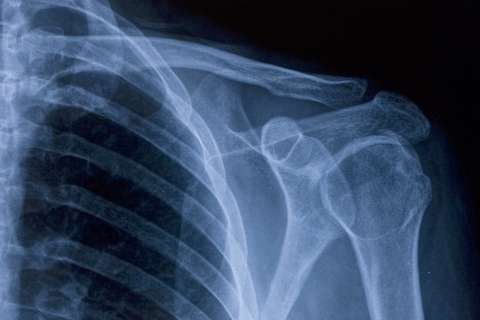

Orthopedic services at UCLA Health address the full range of joint, bone and muscle conditions, from everyday aches to complex injuries. Our orthopedic specialists focus on preventing and treating activity-related injuries so you can move with confidence at any age.

Our team includes orthopedic experts specializing in areas such as spine care, joint replacement, hand surgery and pediatric care. Many people get better with nonsurgical treatments, such as physical therapy or injections. If you do need surgery, you're in expert hands.